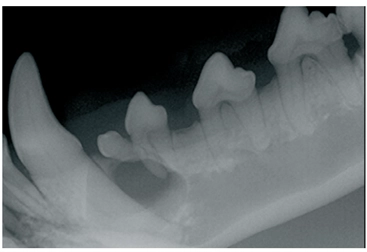

Boksereilla ja muilla lyhytkuonoisilla koirilla esiintyy usein puhkeamattomia hampaita, jotka voivat johtaa follikulaarikystiin eli hammasaihekystiin.

Kysta on nesteen täyttämä rakkula, jota ympäröi ohut sidekudoskapseli. Se voi laajetessaan tuhota leukaluuta ja ympäröiviä hampaita, aiheuttaa leukamurtuman sekä syövyttää viereisten hampaiden juuria. Kystat voivat kasvaa suuriksi jo alle vuoden ikäisillä koirilla.

Puhkeamattomien hampaiden löytämiseksi lyhytkuonoisille koirille suositellaan hampaiston röntgenkuvausta 1–2 vuoden iässä, esimerkiksi muiden terveystarkastusten, kuten lonkkakuvauksen, yhteydessä. On paljon helpompaa poistaa vain puhkeamaton hammas kuin hoitaa myös kystaa.